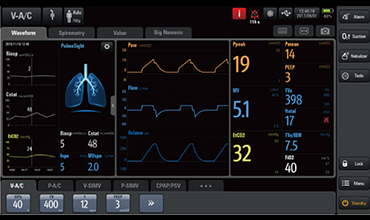

Respiratory Mechanics Monitoring during Ventilation for Severe COVID-19

Respiratory Mechanics Monitoring during Ventilation for Severe COVID-19 -

SV300 Ventilator: A Warrior in the Battle against COVID-19

SV300 Ventilator: A Warrior in the Battle against COVID-19 -